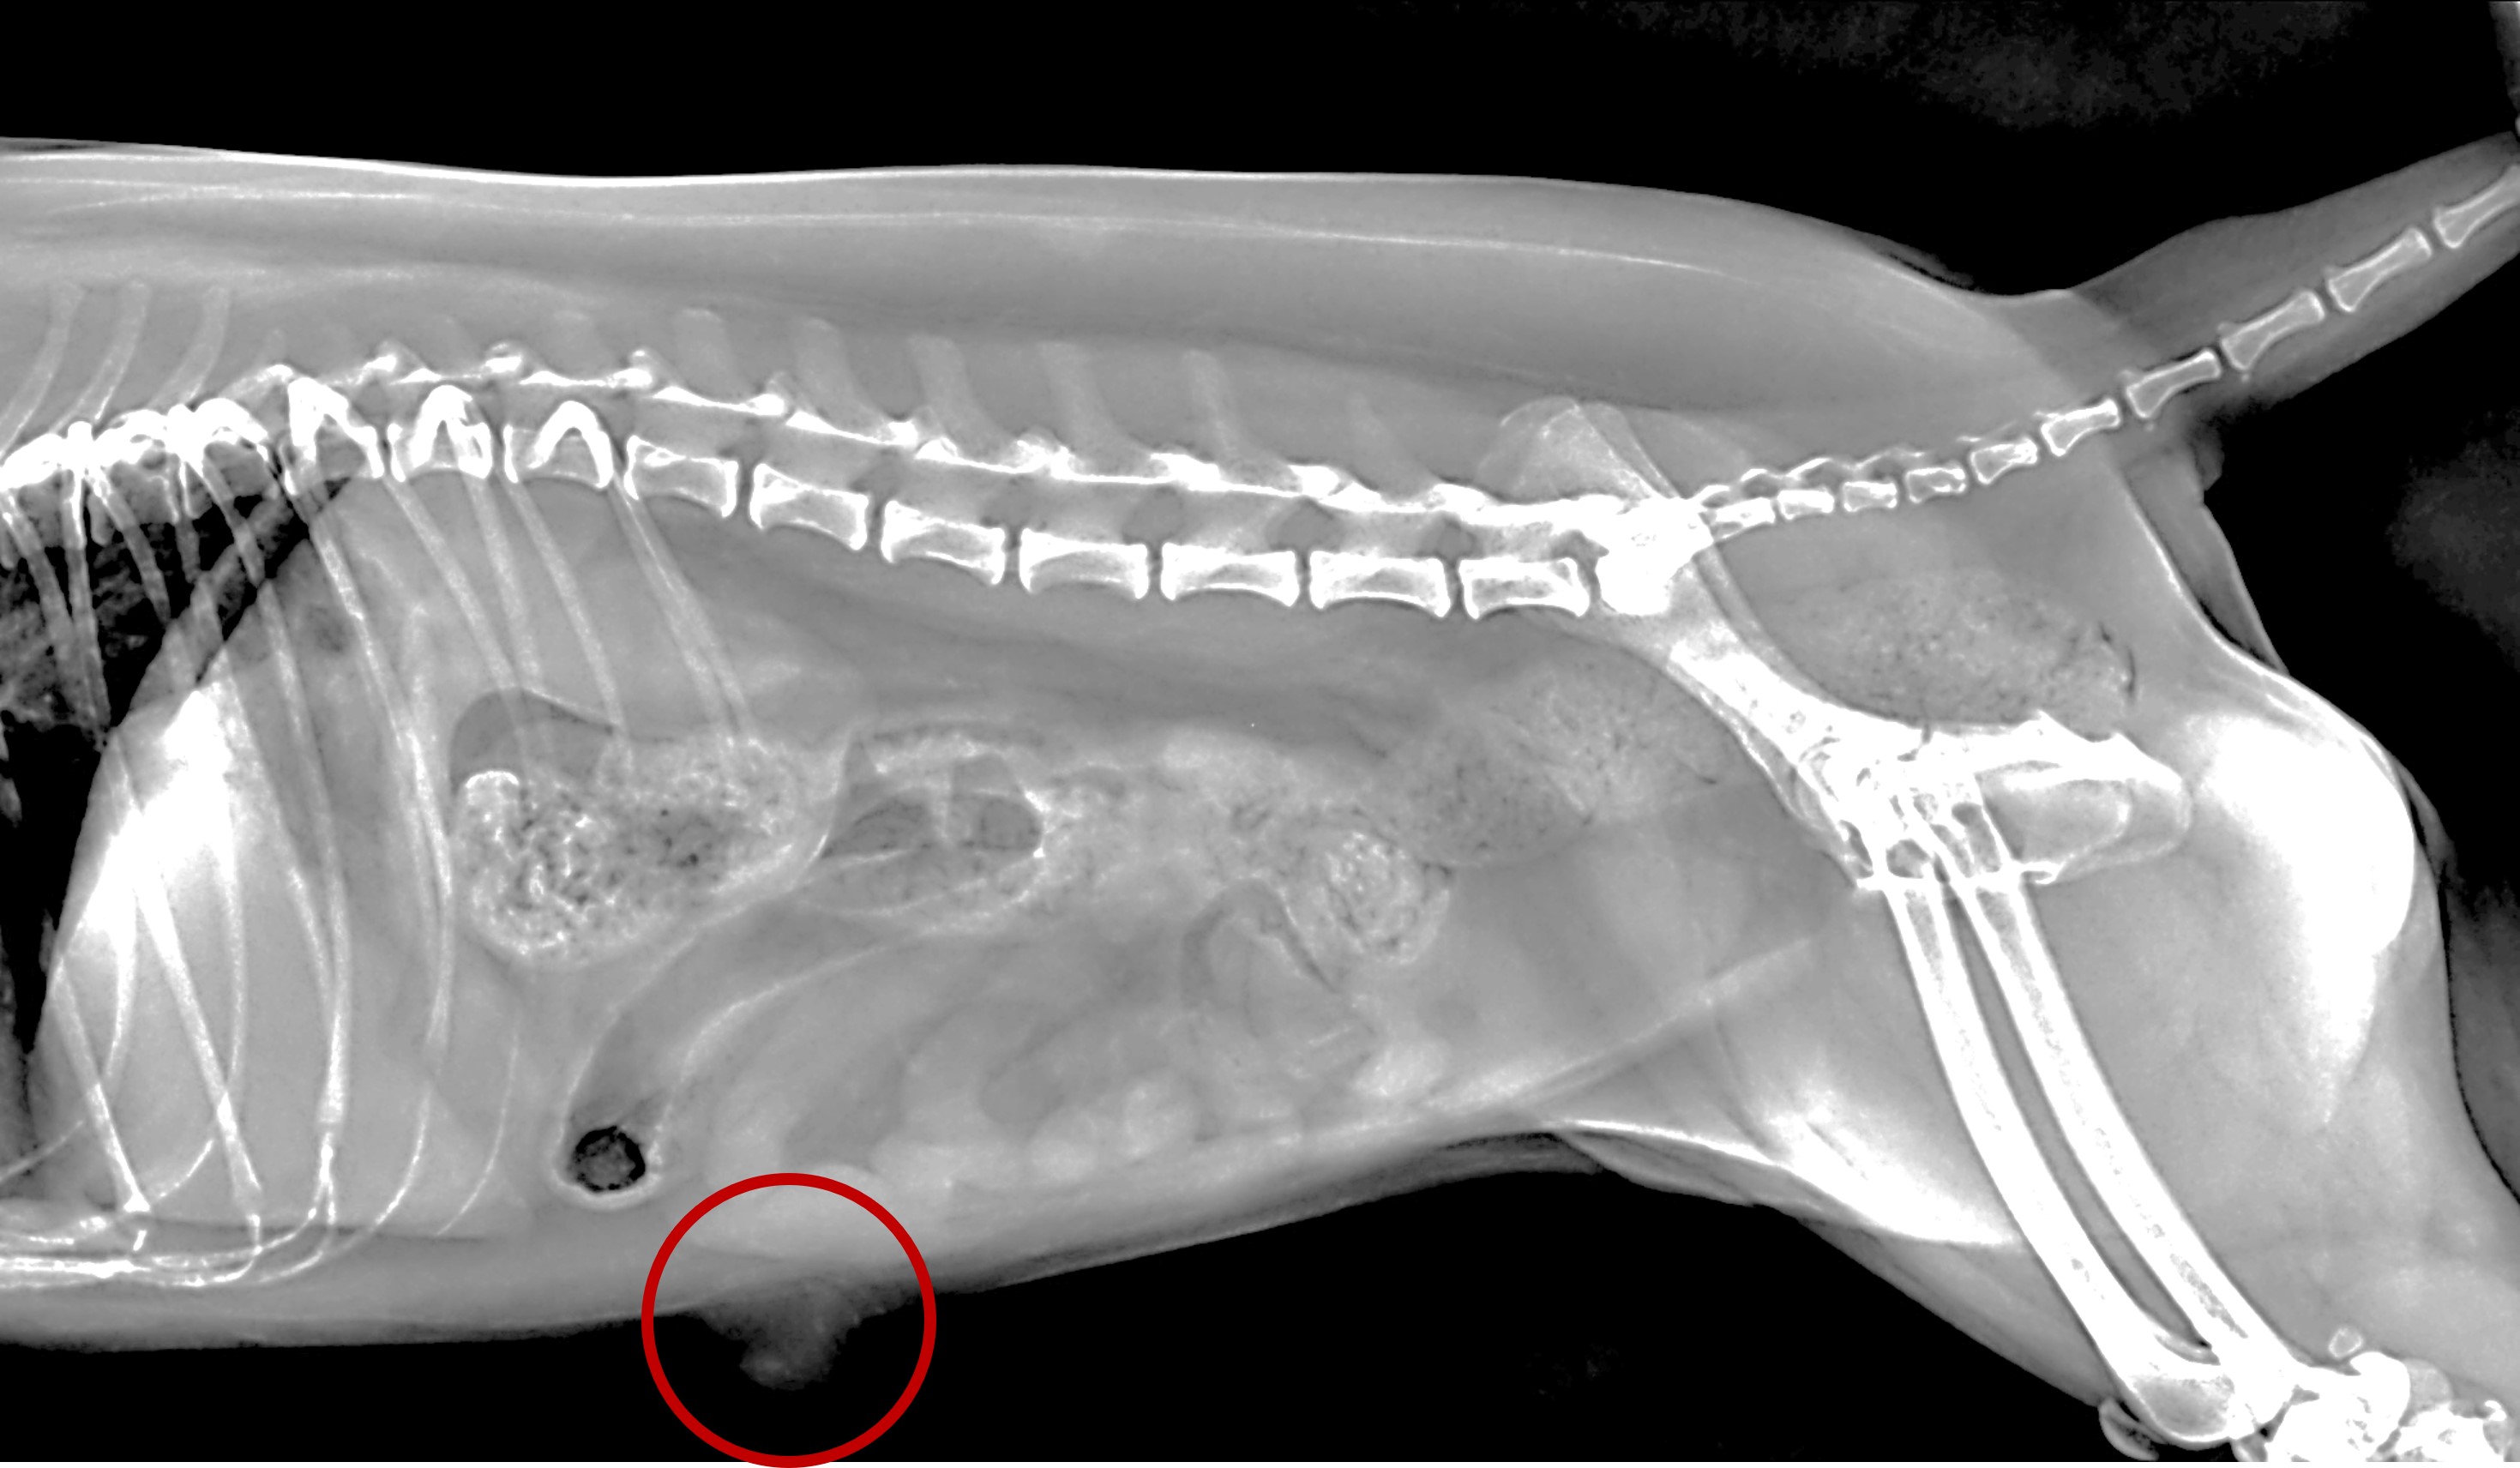

<배꼽탈장 수술 전_배꼽 부위의 복벽 결손으로 복강 내 지방이 탈장된 것이 확인된다>

<복부 방사선 상 배꼽부위에 복벽결손과 그 부위로 지방음영의 조직이 탈장된 것이 확인된다>